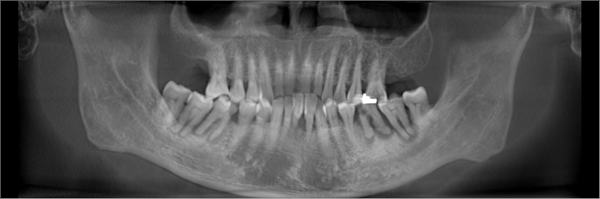

罗家英口内牙齿情况